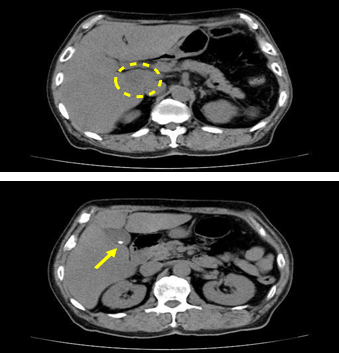

His blood examinations in July 2022 were as follows: TP 7.0 g/dL, Alb3.6 g/dL, ALT 15 U/L, ALT 6 U/L, ALP 44 U/L (38-113), GGT 28 U/L, LDL 70 mg/dL, TG 60 mg/dL, HDL-C 36 mg/dL, BUN 15 mg/dL, Cr 0.97 mg/dL, UA 2.8 mg/dL, Na 134 mEq/L, K 3.4 mEq/L, Cl 97 mEq/L, WBC 9500 /μL, RBC 3.07 x 106 /μL, Hb 10.7 g/dL, Ht 30.9 %, MCV 101 fL, MCH 34.9 pg, MCHC 34.6 g/dL, Plt 35.7 x 104 /μL, fasting blood glucose 118 mg/dL and HbA1c 5.9 %. Other examinations were conducted during Sept 2021 to July 2022. Chest X-ray revealed negative findings, and Electrocardiogram (ECG) showed ordinary sinus rhythm without specific ST-T changes. He received the detail examination of mechanocardiogram and sphygmogram. The results showed that ankle brachial index(ABI)was 1.25/1.29 in right/left, respectively. The values of cardio-ankle vascular index (CAVI) were 8.7/8.5 for right/left, respectively (Figure 2). Furthermore, the results of upstroke time (UT) and % mean arterial pressure (%MAP) were within normal limits. He received abdominal CT scan. Low density area was observed in the caudate lobe of the liver. It was suggested to be due to local infiltration of fat tissue. Furthermore, one gallstone was found in the gall bladder (Figure 3).

Figure 3 Findings of abdominal CT.

3a: Low density area was observed in the tailed leaf of the liver.

3b: One gallstone was found in the gall bladder.

This report showed some figures. Although alcohol intake was related to changes in GGT in Figure 1, no apparent relationship was suggested with changes in body weight. In Figure 2, the presence of clear arteriosclerotic cardiovascular disease (ASCVD) was not suggested in this case from the result of sphygmogram. Gallstones and localized fatty deposits were observed in Figure 3, but moderate or severe fatty liver was not observed, which was expected from history and alcohol intake amount. This patient was initially obese and was able to lose weight by very low-carbohydrate ketogenic (VLCK) diet. For LCD, dose-dependent effect was investigated systematic review for several markers.25 The protocol included 50 trials with 4291 cases. Each 10% decrease of carbohydrate intake showed HbA1c -0.20%, fasting plasma glucose (FPG) -0.34 mmol/L, and weight -1.44kg. Reduction degree was linearly for HbA1c, FPG, weight, TG and systolic BP from 65% to 10%. In contrast, total-Cho and LDL-C showed U-shaped, where greatest weight reduction was -35%. Recent focus includes VLCK diet to obesity and T2D. The study was for 8 RCTs with 648 cases.26 As a result, compared with the control, VLCK showed -0.61% of HbA1c and -2.91kg of weight reduction after 3 months. VLCK diet seems to decrease weight for up to half year against diabetes and obesity. Beneficial effects of HDL and TG would continue until 1 year. For VLCK performance, main limitation may be the lack of carbohydrate restriction for the patient.